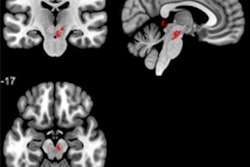

A team of researchers from the University of California, Los Angeles (UCLA) led by Bo Pang and Suraj Doshi trained machine-learning algorithms to identify sleep apnea on diffusion tensor imaging (DTI)-MRI. In testing, the models performed comparably, yielding areas under the curve of 0.84 and 0.85 for diagnosing sleep apnea.

Obstructive sleep apnea is currently diagnosed in a number of ways, including overnight polysomnography at a sleep laboratory. However, this method is costly and requires evaluating many hours' worth of data. In an effort to develop a faster technique, an interdisciplinary UCLA group performed DTI-MRI on 59 people with obstructive sleep apnea and 96 healthy controls.

They then trained and tested two types of machine-learning models -- a support vector machine and a random forest -- to assess mean diffusivity maps from the brain MRI exams for obstructive sleep apnea. Both algorithms showed promising results.